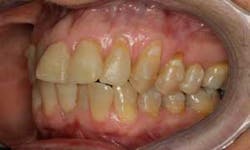

SFOT was used with a high-tech clear aligner to address hard- and soft-tissue deficiencies and severe maxillary and mandibular arch constriction.

A healthy, 57-year-old female presented with a lifelong desire for healthy, straight teeth and a beautiful smile. She had been told numerous times that it was not possible without premolar extractions.